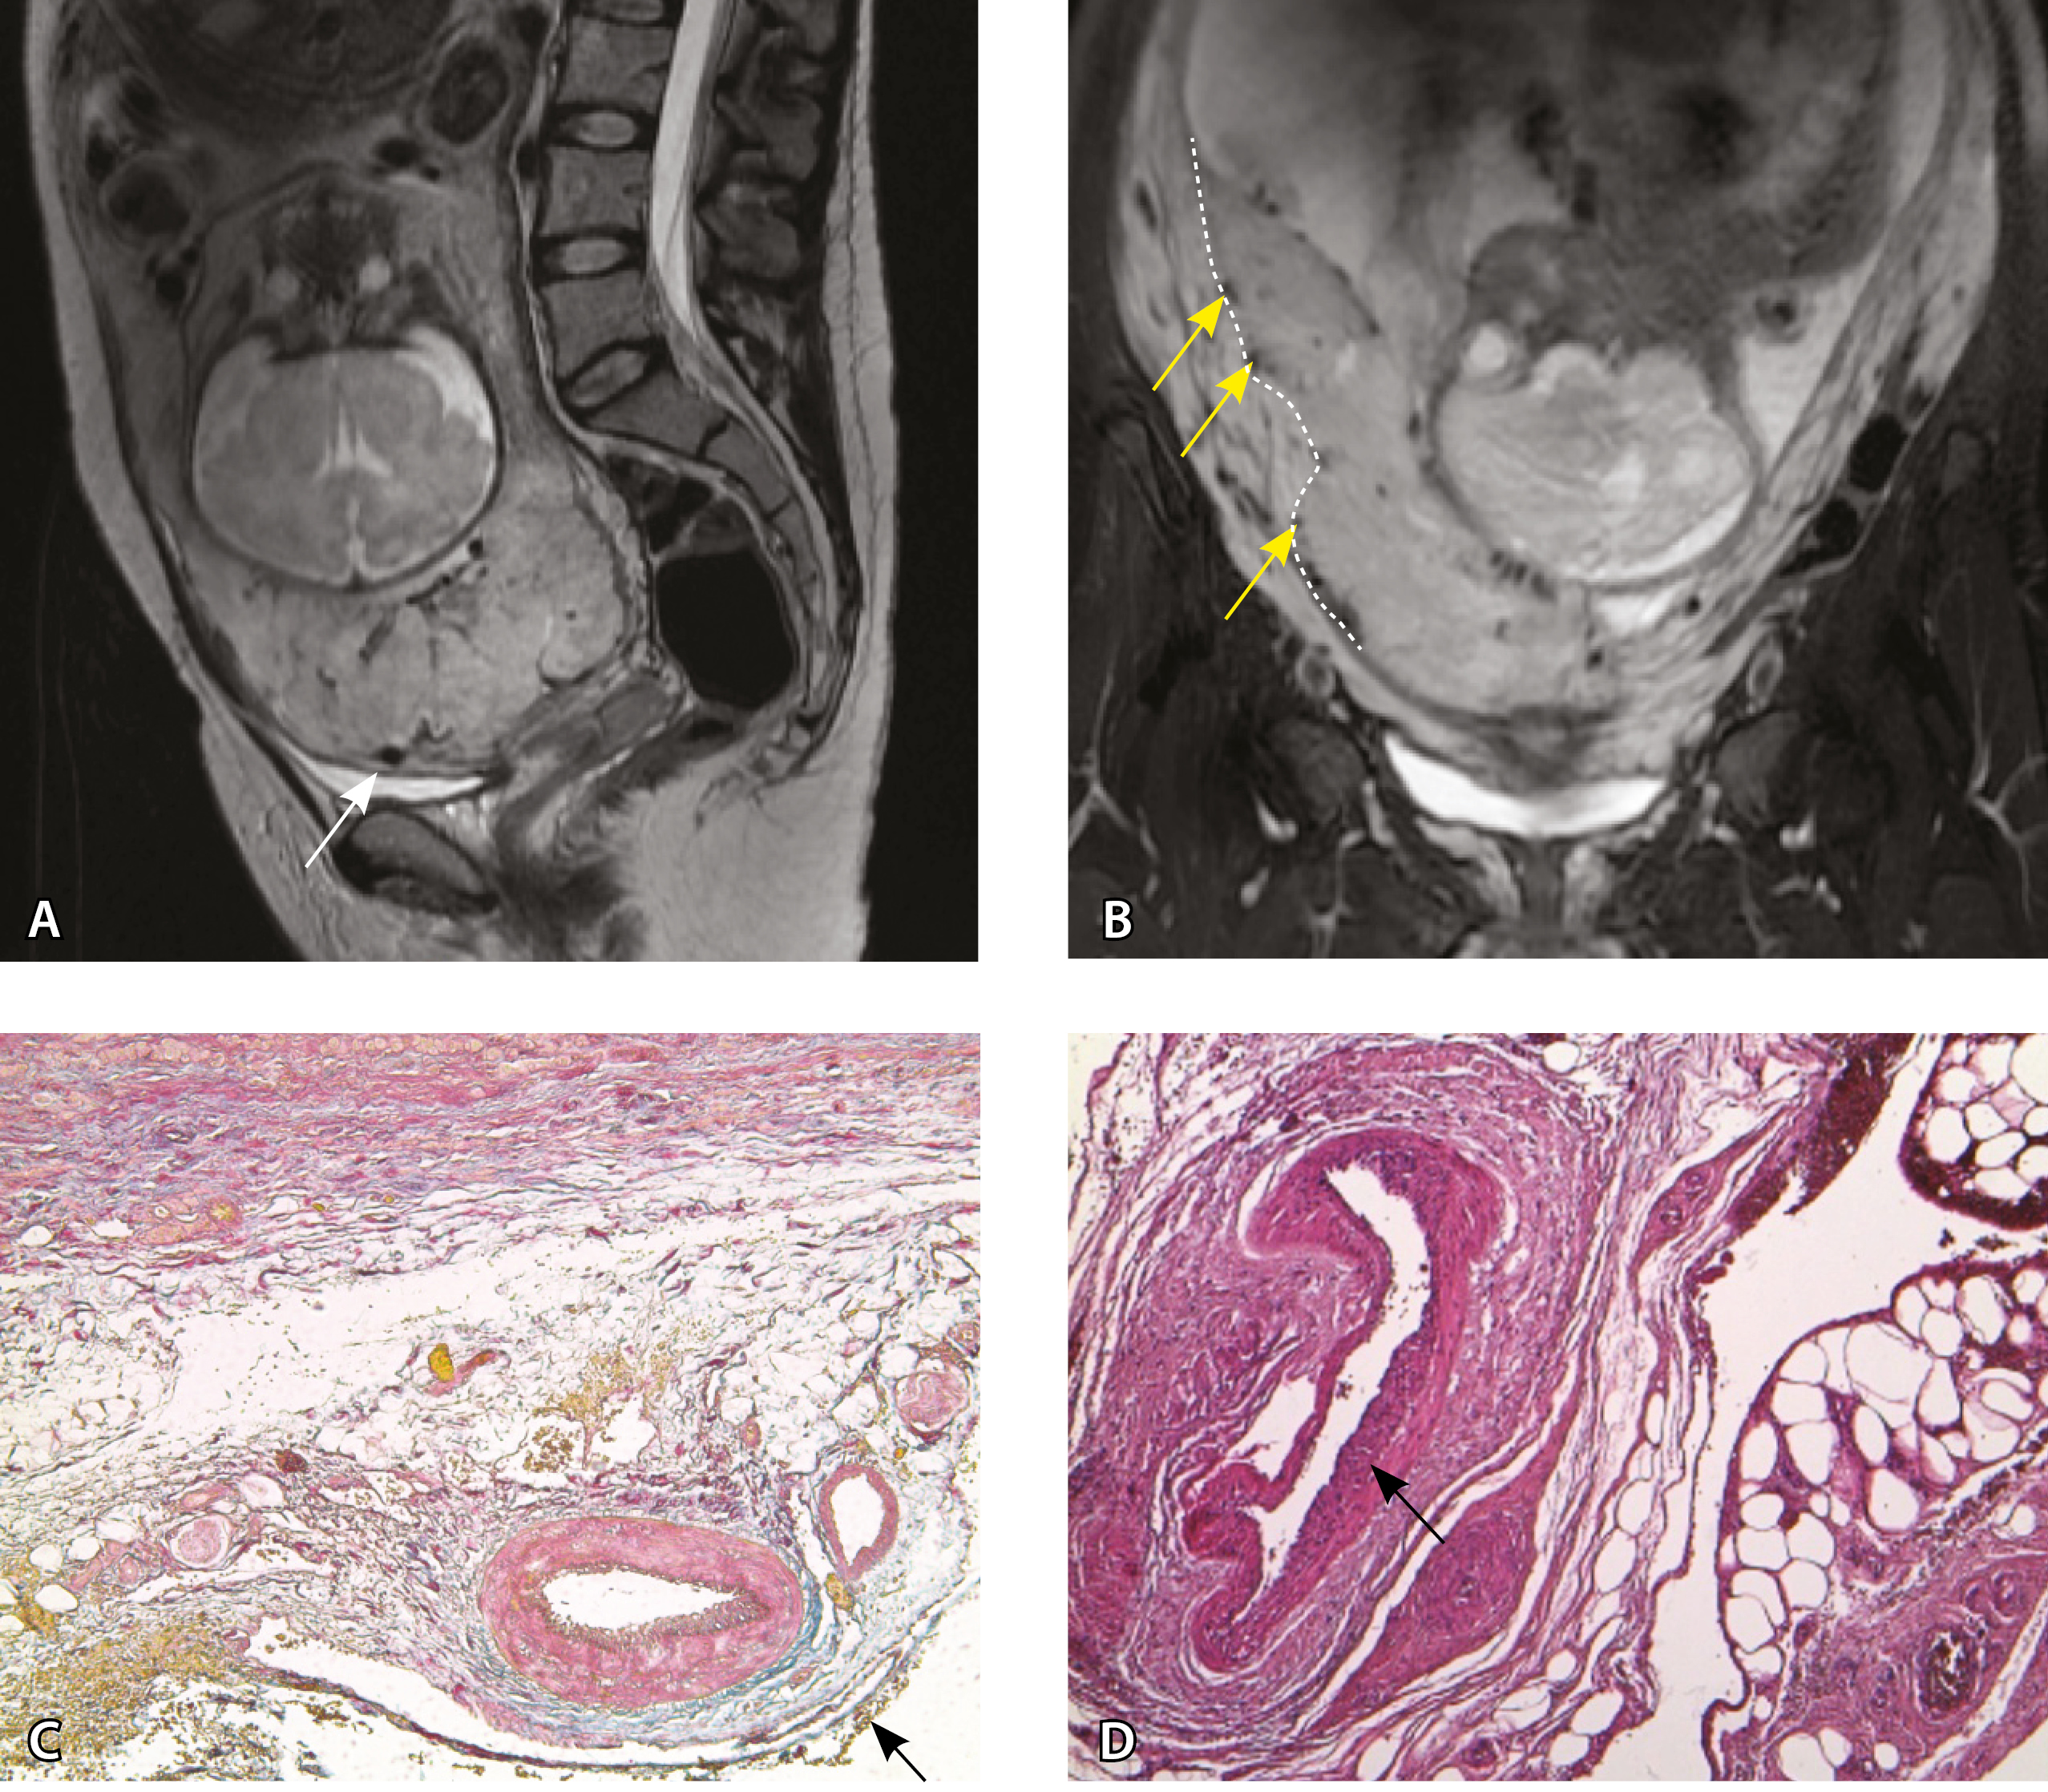

Сосуды 1-го типа. Единичные сосуды в миометрии и пограничных отделах в маточно-плацентарной области (рис. 2).

Рис. 2. Беременность 32 недели, центральное предлежание плаценты без признаков приращения. На магнитно-резонансных томограммах в режиме Т2-взвешенного изображения (Т2ВИ) в сагиттальной плоскости (А) и Т2ВИ с подавлением сигнала от жировой ткани во фронтальной плоскости (Б) видны мелкие ретроплацентарные сосуды, расположенные на границе плаценты и рубца на матке от кесарева сечения (белая стрелка) либо плаценты и миометрия (желтые стрелки; плацентарная площадка указана белой пунктирной линией). Фото микропрепарата: В – визуализируются мелкие артерии и вены в составе серозной оболочки, стрелкой указан слой мезотелия (окраска азокармином по Маллори; × 50); Г – маточно-плацентарный сегмент, стрелкой указан сосуд в толще миометрия на границе с плацентой (окрашивание гематоксилином и эозином; × 50)

В смежных участках строение стенки матки было представлено миометрием с разной ориентацией мышечных пучков и тонкими соединительнотканными прослойками. Сосудистая система состояла из синусоидов – тонких полостей в срединном слое миометрия, а также пре- имущественно мелких артерий в составе серозной оболочки. Только единичные из них визуализировались на МРТ, так как данным методом ввиду технических особенностей невозможно визуализировать самые мелкие сосуды и серозную оболочку матки из-за ее малой толщины. Тем не менее это важно для сравнения картины нормы с последующей гиперваскуляризацией при различных степенях PAS.